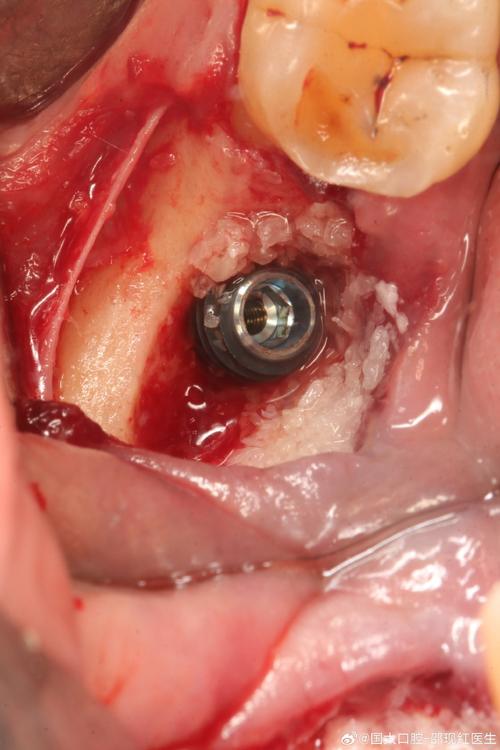

- 植骨手术: 在需要种植的区域进行骨增量。

- 愈合期: 严格遵守医嘱,等待骨愈合(3-6个月或更长),期间保持口腔卫生,避免植骨区域受力。

- 种植体植入: 如果骨条件成熟,即可进行种植手术,将种植体(人工牙根)植入新生骨中。